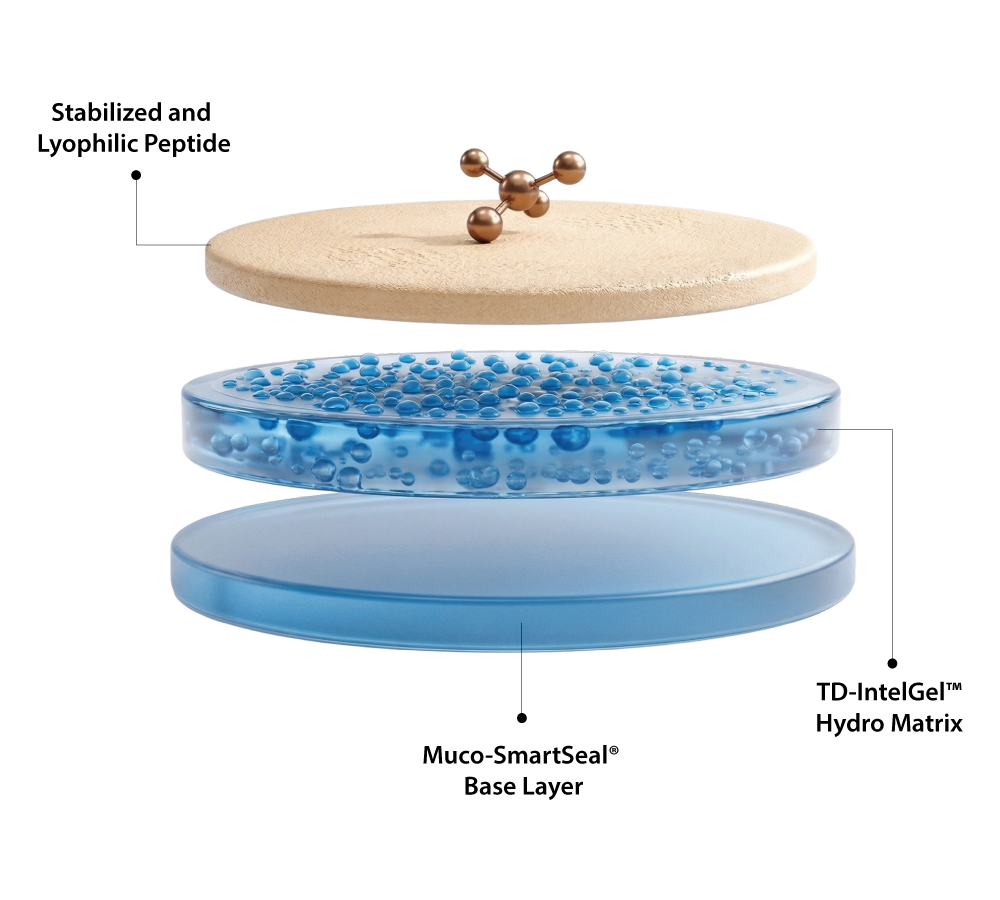

TD-IntelGel™ Coupled with Muco-SmartSeal®

Stabilized Matrix Delivery

Peptides are embedded in a stabilized hydrogel matrix enabling controlled trans-diffusion through buccal membrane with consistent release and enhanced systemic absorption efficiency

Bioactivity Protection

Protects peptides from moisture exposure and enzymatic degradation ensuring long-term structural stability, preserved potency, and maintained biological activity throughout delivery process